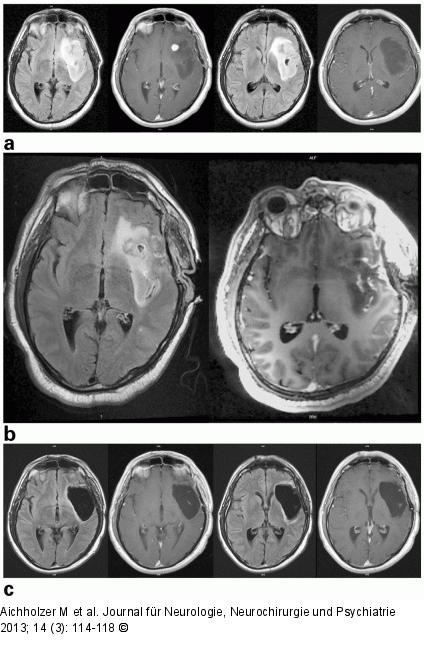

Abbildung 3a-c: iMRT 45-jähriger Patient mit epileptischem Anfall 2009, offener Biopsie am Tumor im Inselbereich 2009 (fibrilläres Astrozytom WHO II), Häufung der epileptischen Anfälle und Tumorwachstum in den MRT-Kontrollen; (a) präoperativ 09/2011 (2× axial Flair/T1 + Kontrastmittel [KM]) mit neuer KM-Aufnahme links frontal; (b) intraoperativ 09/2011 (axial Flair/T1 + KM): KM-affiner Herd ist reseziert, aber noch ausgedehnter Tumorrest in den Randbereichen; (c) 3 Monate postoperativ 03/2012 (2× axial Flair/T1 + KM): geringe Resttumoranteile in den temporodorsalen Anteilen (Histologie: anaplastisches Astrozytom WHO III). |

45-jähriger Patient mit epileptischem Anfall 2009, offener Biopsie am Tumor im Inselbereich 2009 (fibrilläres Astrozytom WHO II), Häufung der epileptischen Anfälle und Tumorwachstum in den MRT-Kontrollen; (a) präoperativ 09/2011 (2× axial Flair/T1 + Kontrastmittel [KM]) mit neuer KM-Aufnahme links frontal; (b) intraoperativ 09/2011 (axial Flair/T1 + KM): KM-affiner Herd ist reseziert, aber noch ausgedehnter Tumorrest in den Randbereichen; (c) 3 Monate postoperativ 03/2012 (2× axial Flair/T1 + KM): geringe Resttumoranteile in den temporodorsalen Anteilen (Histologie: anaplastisches Astrozytom WHO III). |